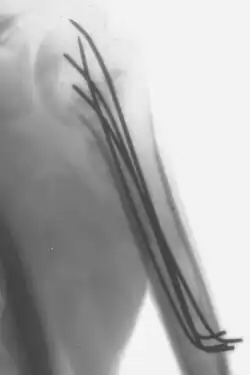

Kirschner-Drähte, auch K-Drähte oder Stifte genannt, sind sterilisierte, geschärfte, glatte Edelstahlstifte. Sie wurden 1909 von Martin Kirschner eingeführt und werden heutzutage weitreichend in der Orthopädie und anderen medizinischen und tierärztlichen Operationen verwendet. Sie sind in verschiedenen Größen erhältlich und werden verwendet, um Knochenfragmente zusammenzuhalten (Stiftfixierung) oder um einen Anker für die skelettale Traktion bereitzustellen. Die Stifte werden oft durch die Haut in den Knochen eingeführt (perkutane Stiftfixierung) mithilfe einer elektrischen oder manuellen Bohrmaschine. Sie sind auch Teil des Ilizarov-Apparats.

- Sie können für eine definitive Fixierung verwendet werden, wenn die Bruchfragmente klein sind (z. B. Handgelenksfrakturen und Verletzungen an der Hand). In einigen Fällen können sie auch für die intramedulläre Fixierung von Knochen wie der Elle verwendet werden.